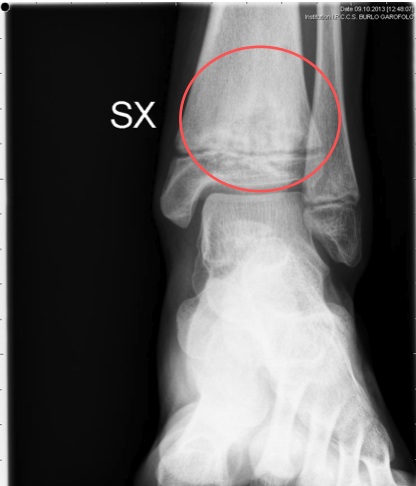

Data la compatibilit� del quadro con una osteomielite cronica multifocale ricorrente (CRMO), abbiamo riconsiderato la diagnosi di AIG oligoarticolare della caviglia e abbiamo eseguito un Rx dell�articolazione (Figura 4) per valutare se anch�essa non rappresentasse una localizzazione di CRMO. L�Rx ha confermato il sospetto evidenziando delle lesioni osteolitiche a carico della metafisi tibiale, compatibili con la diagnosi di CRMO. Abbiamo cos� eseguito una RMN total body che ha escluso ulteriori localizzazioni.

Figura 4. Rx caviglia sinistra.